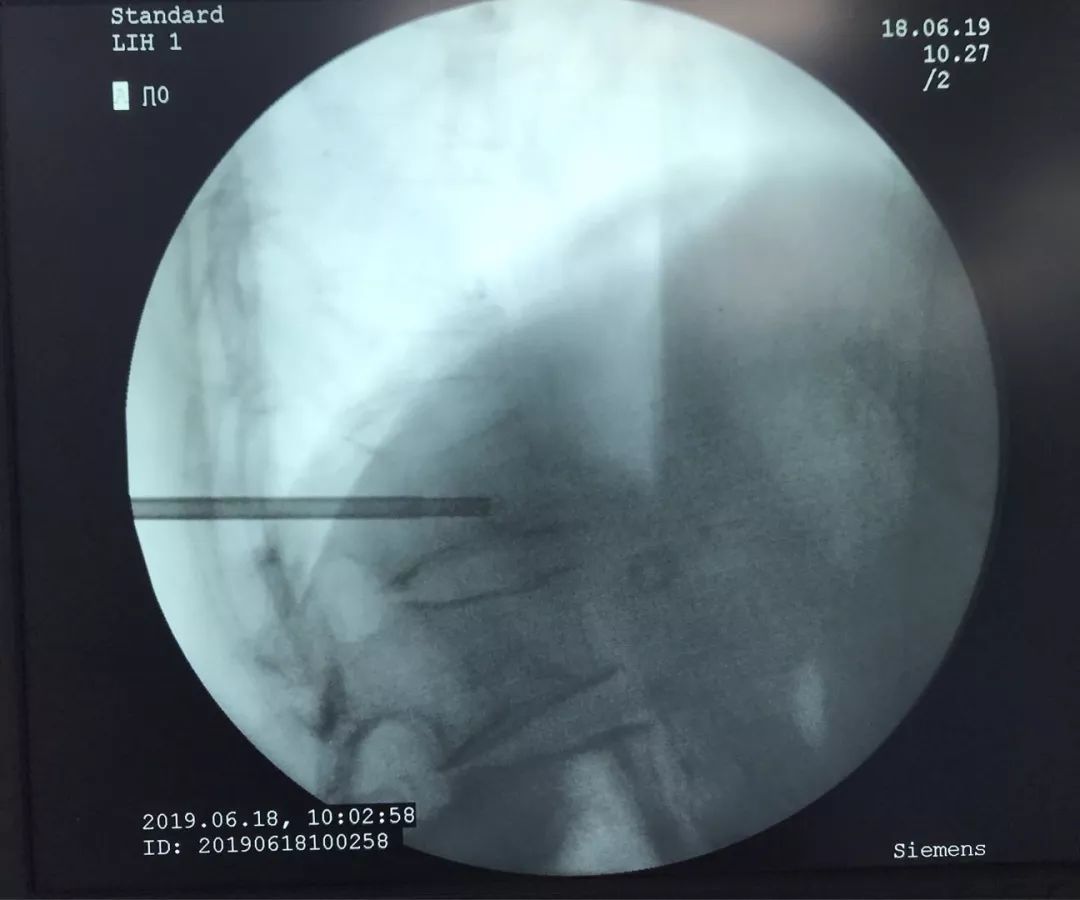

术中椎体穿刺时,椎体密度显著下降,穿刺阻力显著降低,引流暗褐色血性液体,送病理检测。

骨水泥灌注术中

灌注骨水泥既可以起到椎体成型的作用,还可以起到止痛的作用。如果是椎体肿瘤,还可以对肿瘤细胞起到杀灭的作用。